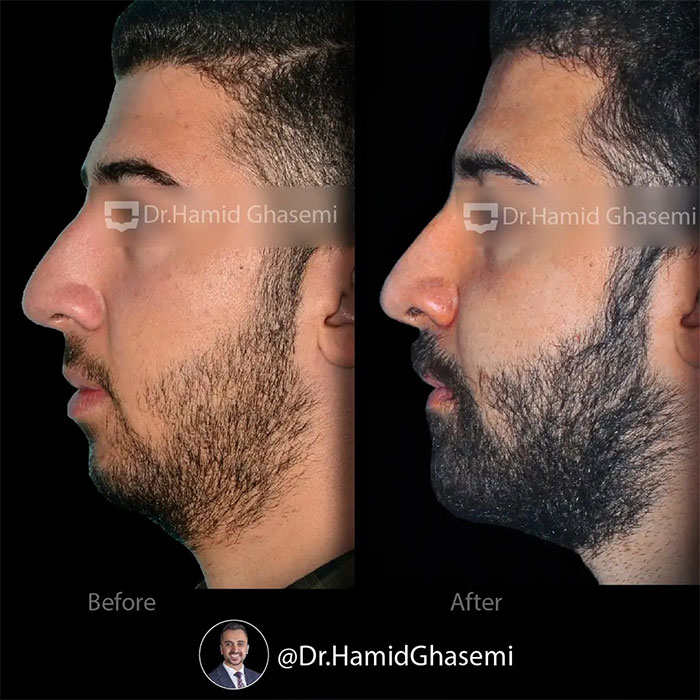

شماره پرونده : M.97_1321

درمان ارتودنسی همراه با جراحی هر دو فک در کیس open bite + long face در مدت ۲۴ ماه انجام شد. دندانهای نیش فک بالا جایگزین دندانهای غایب لترال شدند.

Orthodontic treatment with surgical procedure on both arches done for long face + open bite case within24 months. Upper canines substituted for missing upper laterals.